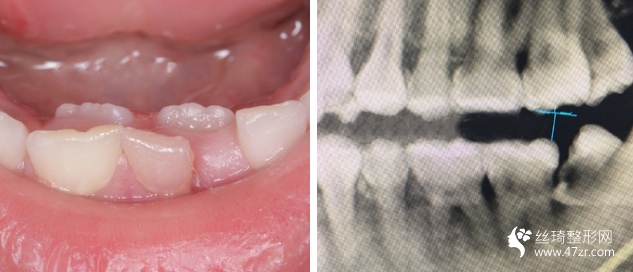

3.南京友誼整形外科醫(yī)院沈宏瑜主治醫(yī)師案例展示

一直以來(lái),我算是一個(gè)對(duì)自己要求比較高的人,見(jiàn)不得自己有任何的瑕疵,就連牙齒也不行。 所以在我開(kāi)啟牙齒矯正路途前的三個(gè)月里,我托了較為多人進(jìn)行行業(yè)摸底

我的牙齒其實(shí)問(wèn)題不大,但是下面兩個(gè)牙齒被擠的歪了出來(lái),而且我 一直覺(jué)得我的嘴有點(diǎn)往外凸出,所以一直都有矯正的想法,朋友在他 們家做的貼面,推薦給我說(shuō)薇琳醫(yī)生很專業(yè)的,所以我也就過(guò)來(lái)了。 首先做了檢測(cè),然后設(shè)計(jì)了方案,取模,然后根據(jù)自己的牙齒情況制 定矯正器。 耐心等待我矯正器的到來(lái)。